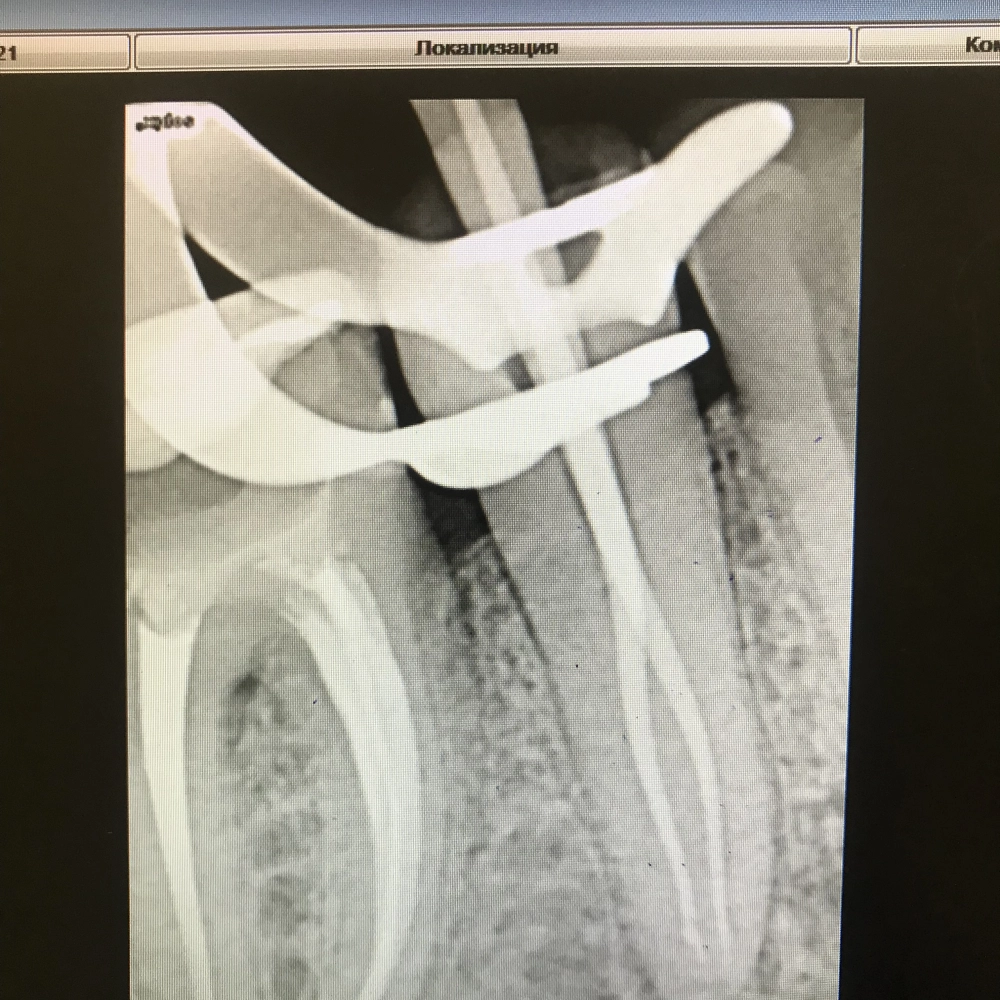

Извлечение инструмента из корневого канала зуба

Извлечение фрагментов инструмента из каналов с помощью микроскопа

от 10000 руб.